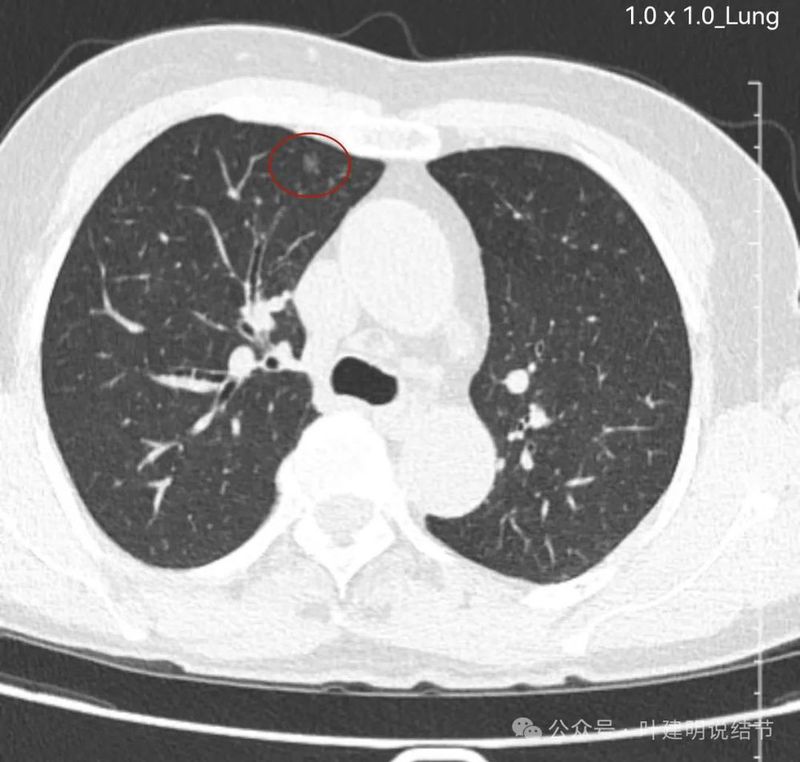

右上混合密度结节,有血管进入,有实性成分,磨玻璃部分轮廓与边界清,与恶性较为符合,浸润性腺癌可能性较大点。当然由于首次发现,先抗炎后再复查更为稳妥些,有时炎性也会边界较清的。

左上叶磨玻璃结节,密度稍不均,有部分偏实性成分,表面不平,轮廓与边界清,似有微小血管进入,恶性范畴的可能性大些。